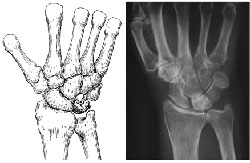

The lunate bone begins to harden due to the lack of blood supply during Stage 2. This hardening process is called sclerosis. In addition, the lunate will appear brighter or whiter in areas on x-rays, which indicates that the bone is dying. To better assess the condition of the lunate, your doctor may also order either MRI scans or computed tomography (CT) scans.

The most common symptoms during this stage are wrist pain, swelling, and tenderness.

Stage 2. (Left) This illustration shows that the lunate has hardened with more than one fracture line. (Right) The lunate is brighter than the surrounding bones, which indicates that the bone is dying.

Reproduced and adapted with permission from Allan CH, Joshi A, Lichtman DM: Kienböck's disease: diagnosis and treatment. J Am Acad Orthop Surg 2001; 9 : 128-136.